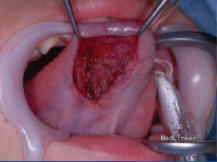

患者八岁,发现舌部有一逐渐生长的肿物一个月,没有其他不适。患者患有共济失调 - 毛细血管扩张症。

检查发现舌下有一隆起,约1.2*1cm大小,未影响舌功能和运动,唾液分泌正常,周围淋巴结无肿大。 影像检查显示右舌有一不规则圆形肿物,边界不清。

初步诊断为涎腺肿瘤,如多形性腺瘤。然而,由于患者被诊断为共济失调 - 毛细血管扩张症,考虑恶性淋巴瘤的可能性较大。全麻下手术切除,术后配合化疗。病理结果显示为弥漫性大B细胞淋巴瘤。